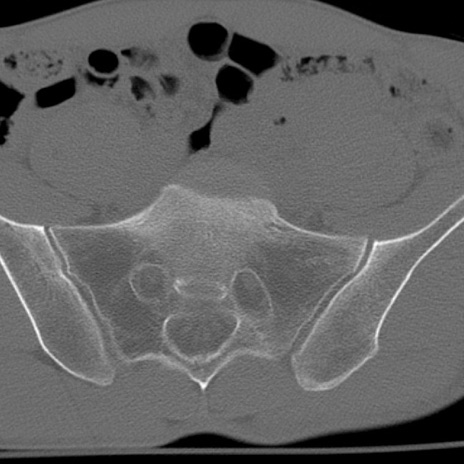

症例3 腰椎CT(横断像)

腰椎CT